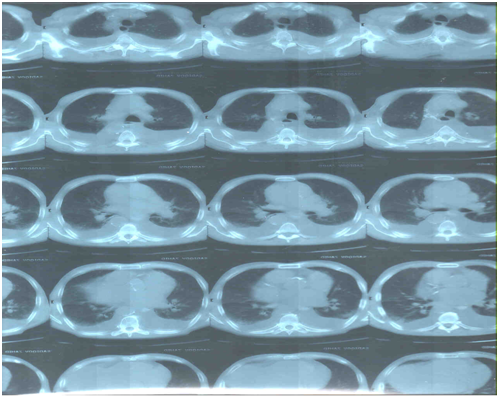

Фигуры